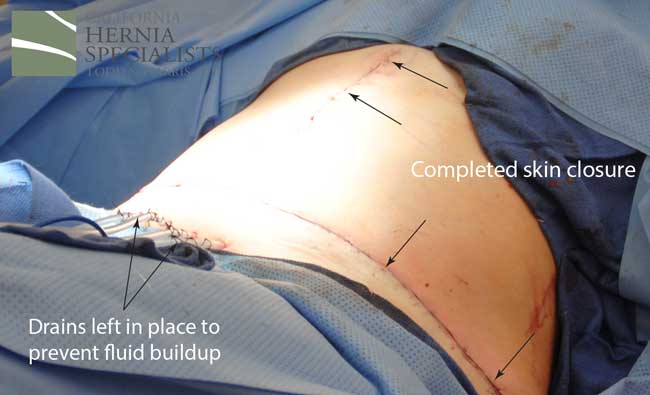

This technique requires more surgical time, recovery time, and usually several days in the hospital. However, this patient chose to proceed with the open hernia repair. Below are some of the pictures from his surgery as well as post operative CT scan image and photos of the patient.

Instead we discussed open hernia repair with a large incision to repair the damaged muscle and to remove excess skin and fat once the muscle was repaired. Below are a number of pictures including before and after photos, as well as photos taken during her surgery.

Because this patient had failed two prior surgeries, we performed a complex open hernia repair on him. This repair included a technique called ‘component separation’, where the oblique muscles on the sides of the abdomen, are partially released, or cut, to allow the rectus muscles to be pulled back together in the middle of the abdomen.

Since the abdominal muscles were weakened, we placed a sheet of biologic mesh under the muscle in the middle at the area of the hernia hole, closed the muscle over this mesh, then placed another mesh on top of the muscles which were closed. This provided him with three layers of repair.

The CAT scan image below compares the patient before surgery, and then after surgery when the muscle has been pulled back together and the hernia has been repaired.

The patient is doing great months after his surgery with no bulge, no pains, and the ability to return to normal activities. He’s lost close to 40 pounds since he can now exercise again and is feeling back to normal.